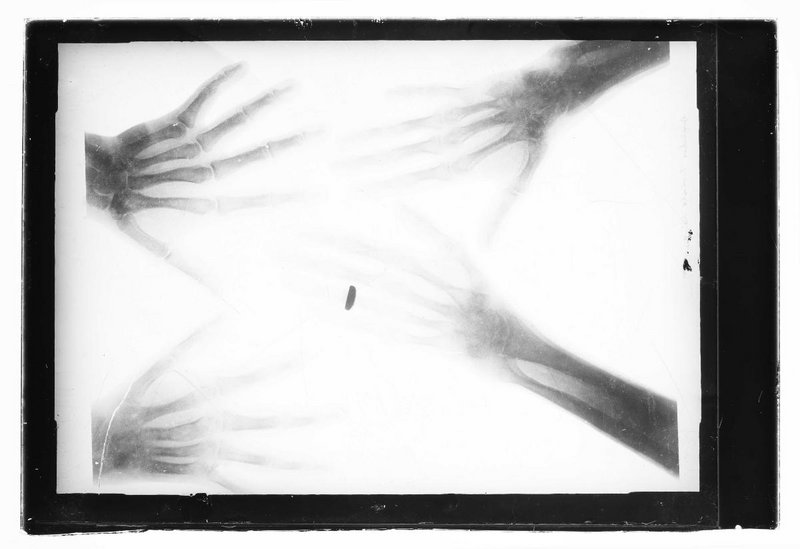

Laut Diagnose von Franz Kainberger, Prof. Dr., Medizinische Universität Wien, Wien, vom 17.7.2020 sind Fälle von Arachnodaktylie (Spinnenfingrigkeit) sichtbar. Das Motiv ist verkleinert, daher wurde diese Aufnahme für eine Reproduktion in Publikation angefertigt.